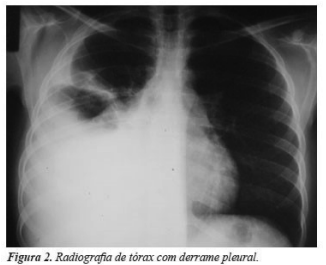

Um homem de 28 anos, com doença de Chron, está há 6

semanas em uso de adalimumabe após pesquisa para TB negativa.

Queixa-se de tosse seca, febre vespertina e dispneia há 7 dias.

Realizou RX de tórax, conforme figura abaixo. Considerando a

principal suspeita clínica, deveria ser solicitado, na análise do

líquido pleural para melhor elucidação diagnóstica, a: